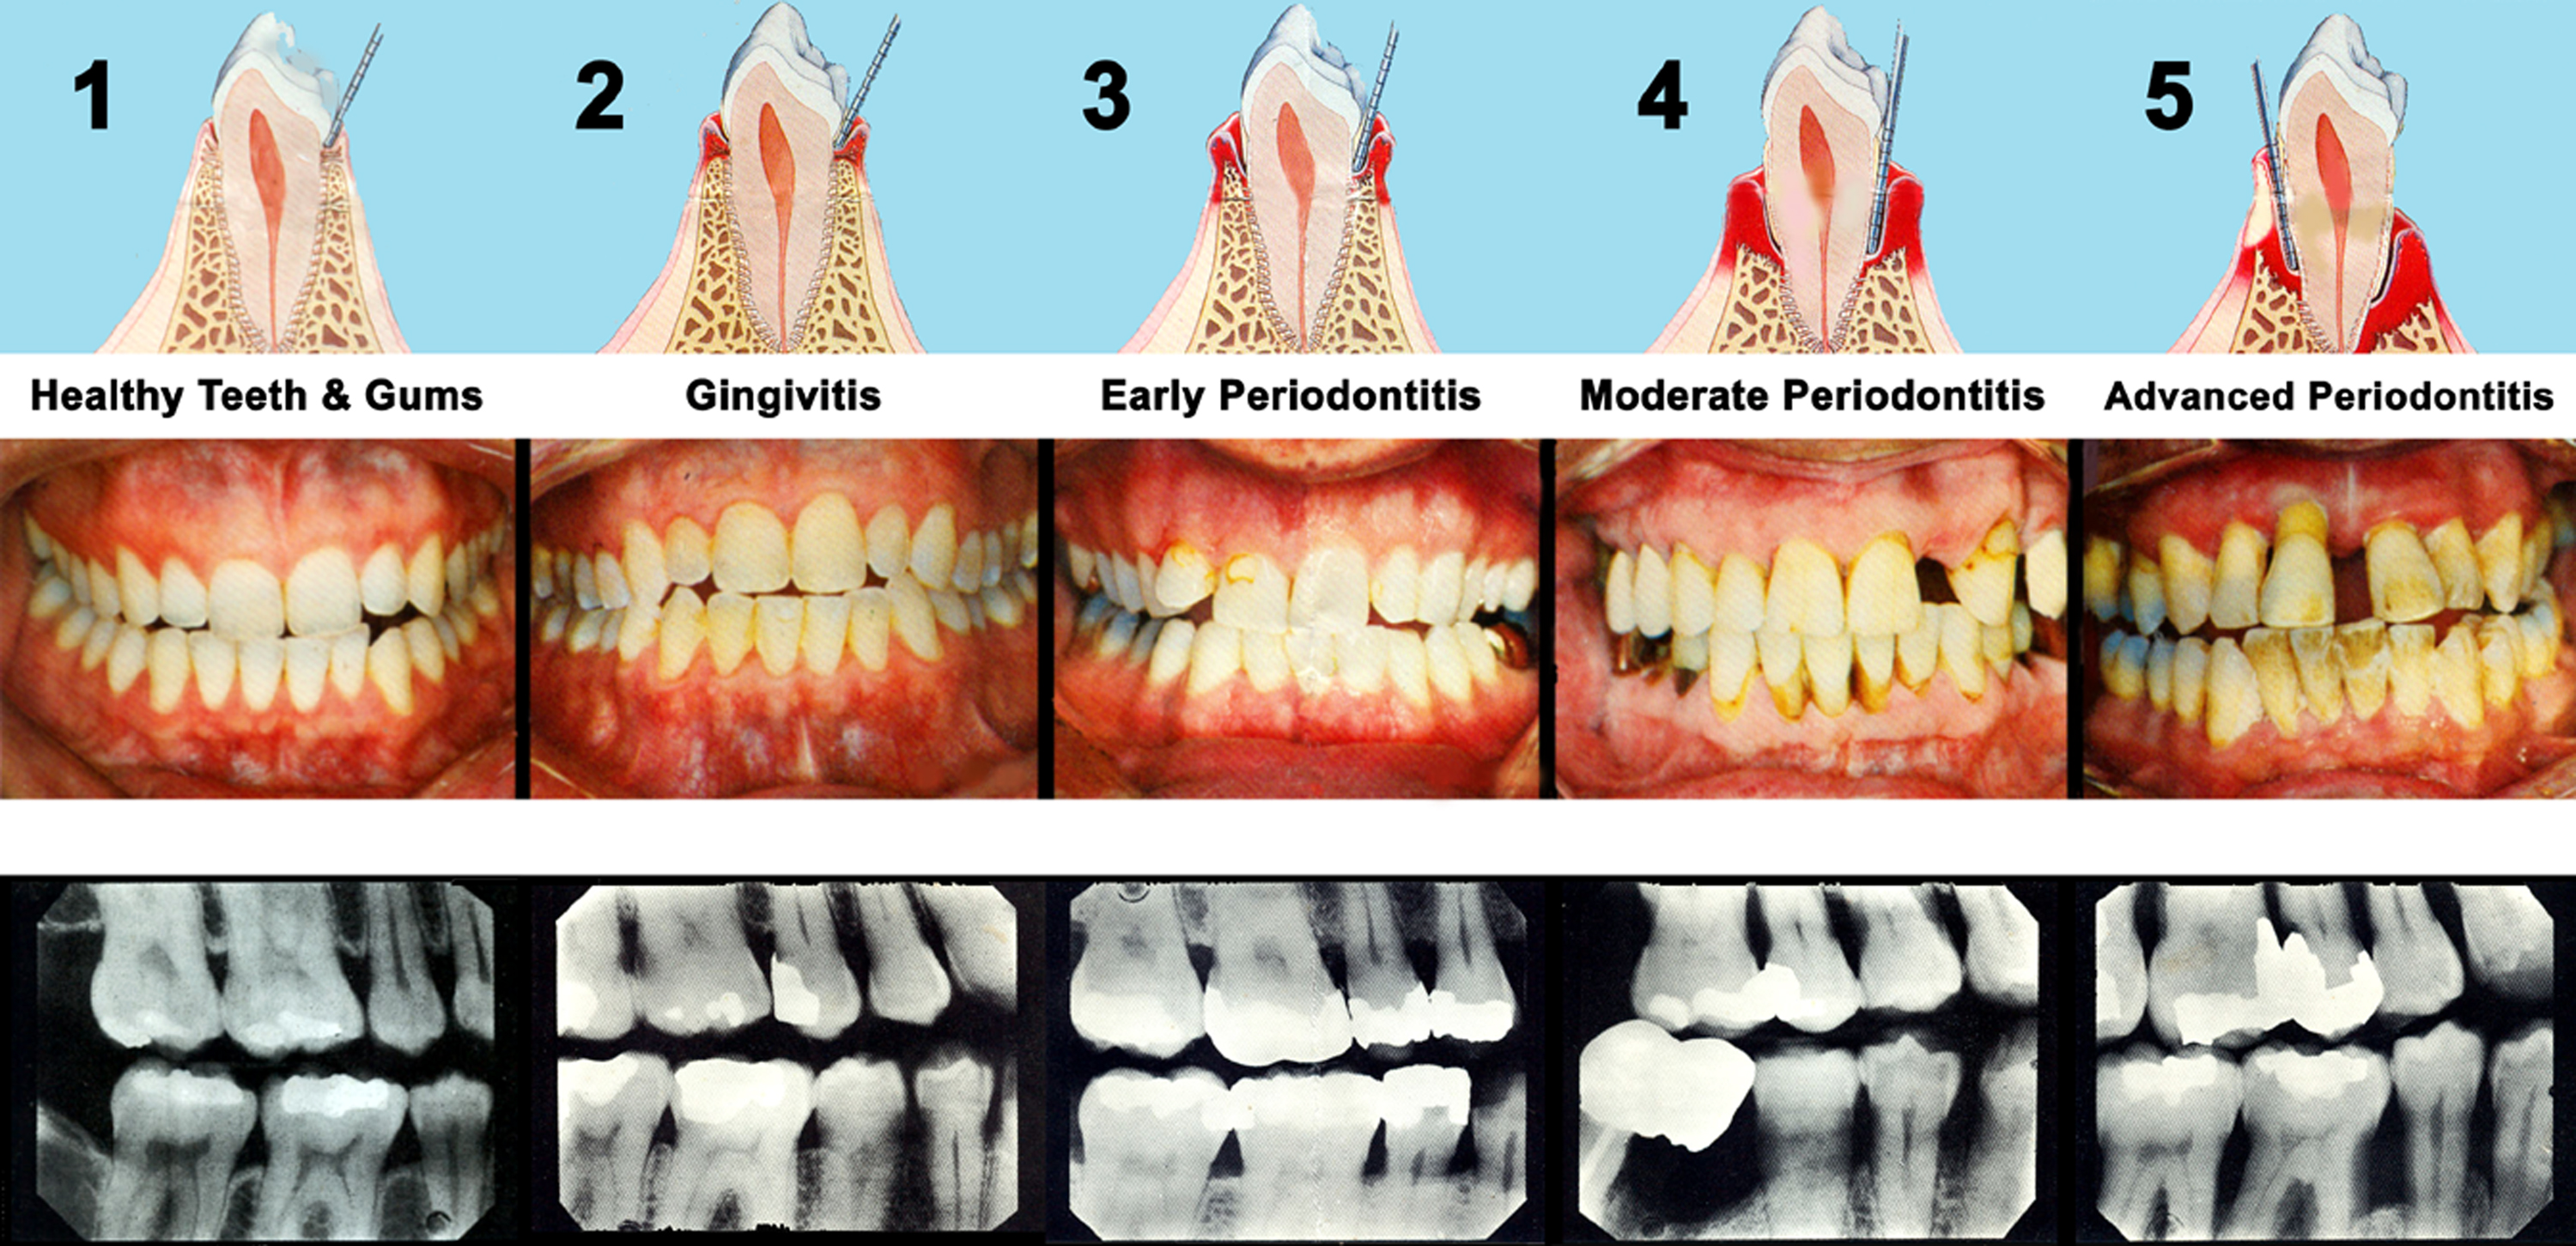

2. Gum Disease (Periodontitis)

Severe gum disease can cause the gums to recede from the teeth, creating pockets where food particles and bacteria can become trapped. These pockets can become infected, potentially leading to abscesses.

Gingivitis

Gingivitis is the earliest stage of gum disease, an infection of the tissues around your teeth caused by plaque.

If you have gingivitis, your gums may become red, swollen and bleed easily. You may also experience bad breath. Because gum disease is usually painless, you may not know you have it.

You are more likely to develop gum disease if you skip brushing and flossing, use tobacco, have crooked teeth that are hard to keep clean, are pregnant, have diabetes or take certain medications. When in its early stages, the disease is still reversible and your gums can be returned to good health with a professional cleaning from your dentist, along with daily brushing and flossing.

Periodontitis

Periodontitis is the more advanced form of gum disease, a major cause of tooth loss in adults. According to the CDC, nearly half of U.S. adults suffer from it. The disease can be reversed in early stages, but damage may be permanent the longer it goes untreated. Although you may not be aware of the gum disease in your mouth, abscesses can develop which usually painful. Symptoms include bleeding, swollen gums, persistent bad breath or bad taste, loose permanent teeth and a change in bite. Your teeth may appear to become longer as gums and bone recede. There are many treatments available, including deep cleanings known as scaling and root planing. Talk to your dentist to find out what’s best for you.